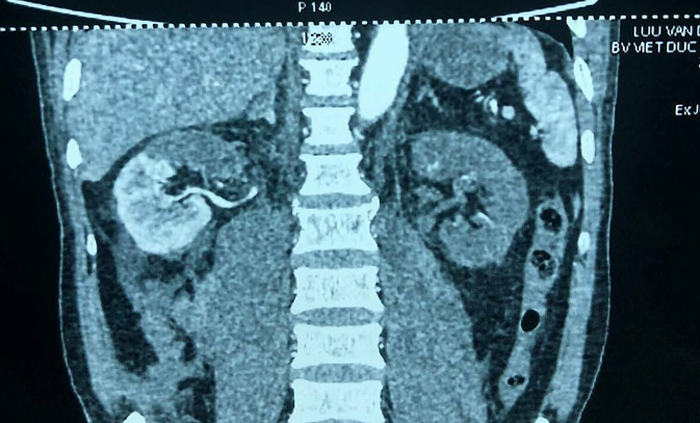

Người bệnh trước đó bị tai nạn giao thông, bác sĩ ở Bệnh viện Hải Dương chẩn đoán chấn thương cột sống, chuyển tới Bệnh viện Việt Đức. Kết quả chụp chiếu cho thấy thận bên phải của bệnh nhân bị mất một nửa chức năng, thận bên trái thiếu máu, mất chức năng hoàn toàn. Chức năng thận giảm, có biểu hiện suy thận.

Phim X-quang trước mổ cho thấy thận phải mất 1/2 chức năng, thận trái mất hoàn toàn. (Ảnh: BSCC)

Nếu bệnh nhân không có biểu hiện suy thận, có thể không ghép thận tự thân và sống bằng thận còn lại. Bệnh nhân này đã có dấu hiệu suy thận, bác sĩ bắt buộc phải tiến hành ghép thận tự thân để hai thận vẫn bổ sung chức năng cho nhau.